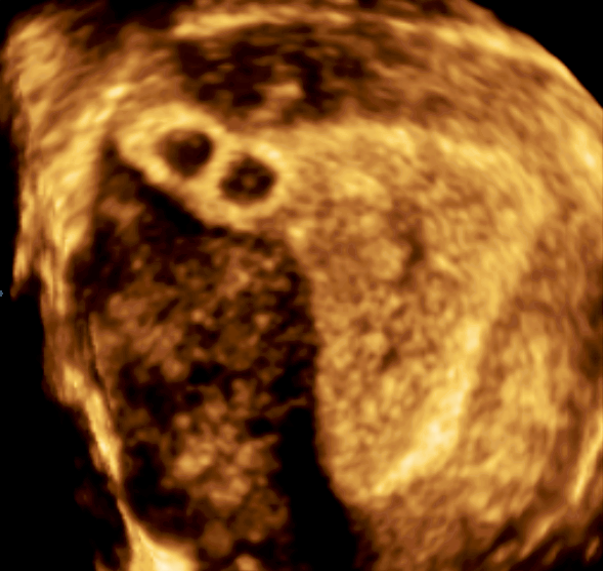

Современные экспертные УЗИ сканеры дают возможность проводить исследования всех органов в 3D. Это позволяет, используя полученный массив данных, получать диагностические сечения в любой плоскости, недоступной для обычного 2D УЗИ. Наиболее интересной является фронтальная. Например, визуализация полости матки. Диагностическая возможность выявления пороков развития превосходит все другие методы (рентгеновские и МРТ). Метод также позволяет уточнить положение ВМК (спирали) в полости матки, расположение миоматозных узлов, расположение плодного яйца на малых сроках, полипов. Сегодня современное экспертное ультразвуковое исследование невозможно без использования 3D УЗИ.